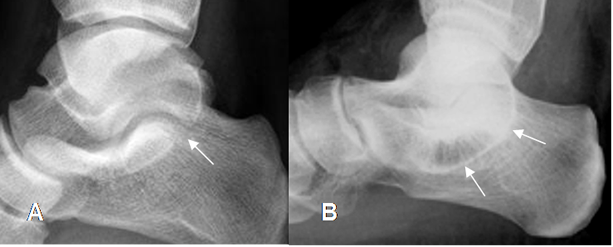

En la Rx simple y el TAC hay formación de puentes, en las coaliciones de tipo óseo. En las fibrosas y cartilaginosas los huesos están muy juntos y con irregularidad en sus contornos. (26). (Fig 135 A y B y 136 A y B).

Fig 135 B. Coalición ósea del tarso.

A: Rx AP. Fusión y formación de puente óseo entre el escafoides, cuboides y la cuña lateral.

B: TAC coronal y C: RM T1 coronal. Coalición ósea talocalcánea, en la parte medial.

Fig 138. Coalición del tarso.

A y B: Rx lateral del tobillo. Signo de la “C” incompleto, como hallazgo normal en A. En B el signo de la “C” es completo, por coalición talocalcánea.